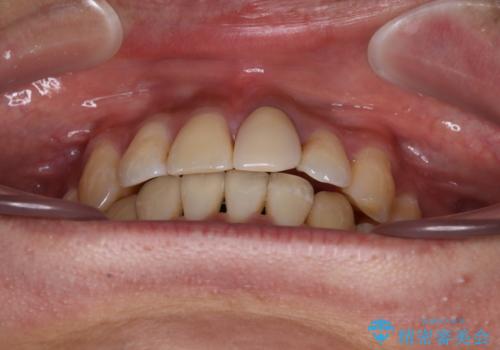

- 下顎の八重歯を気にして来院された患者様です。

左下以外、3本の第一小臼歯が既に抜去されており、左下は八重歯になっている状態でした。

左下の八重歯は手前に傾斜していたため、インビザラインによる抜歯矯正が可能と判断し、後方にある第一小臼歯を抜歯してインビザラインにて矯正治療を行うこととしました。

ワイヤー矯正と比較すると、八重歯が後方に傾斜した仕上がりとなりましたが、患者様ご希望のインビザラインにて十分な歯列を達成することができました。